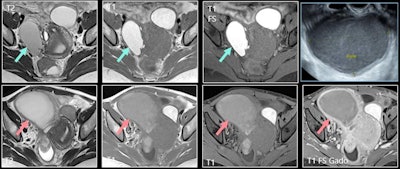

The sonographic appearance may be similar to an uninfected endometrioma. On MRI, there is an increase in the size of a known endometrioma, as well as a reduced typical endometriotic signal (loss of hyperintensity in T1-weighted FS imaging and loss of shading in T2). Other signs are marked restriction of diffusion with very low apparent diffusion coefficient (ADC) values, thick enhanced walls, and pelvic stranding.

"Superinfected endometriomas lose their typical endometriotic MRI signal and show marked restriction of diffusion with low ADC values," noted Mandoul and colleagues.

Hemorrhage is also rare, occurring in approximately 2% of cases and comprising fissuration or rupture of an endometrioma. On MRI, a hemoperitoneum with markedly hyperintense fluid may be seen on fat-suppressed T1-weighted images (i.e., the same signal as the endometrioma). Acute hemorrhage caused by other conditions usually has intermediate or slightly high signal intensity on T1-weighted FS images. Distorted shape of the endometrioma is another aspect to look out for.

"Fat-suppressed [T1-weighted] images are mandatory," the authors pointed out. "Markedly hyperintense peritoneal fluid is characteristic of rupture of an endometrioma. Fissurated or ruptured endometrioma show a distorted shape."